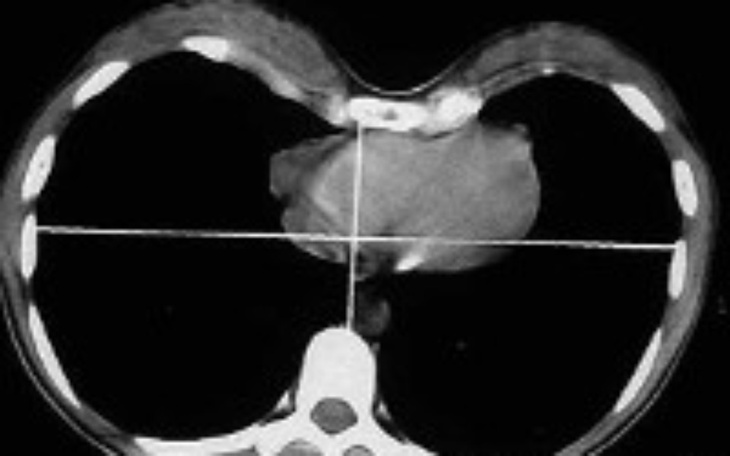

Mostek coraz bardziej zbliża się do jego serduszka co może stanowić poważne zagrożenie życia.

Żeby udało się naprawić tak złożoną deformację klatki syna ,oraz ocalić serduszko przed uciskiem potrzebna będzie odpowiednia Orteza robiona na zlecenie aż w Stanach Zjednoczonych .Koszt takiej ortezy to aż 10000 zł